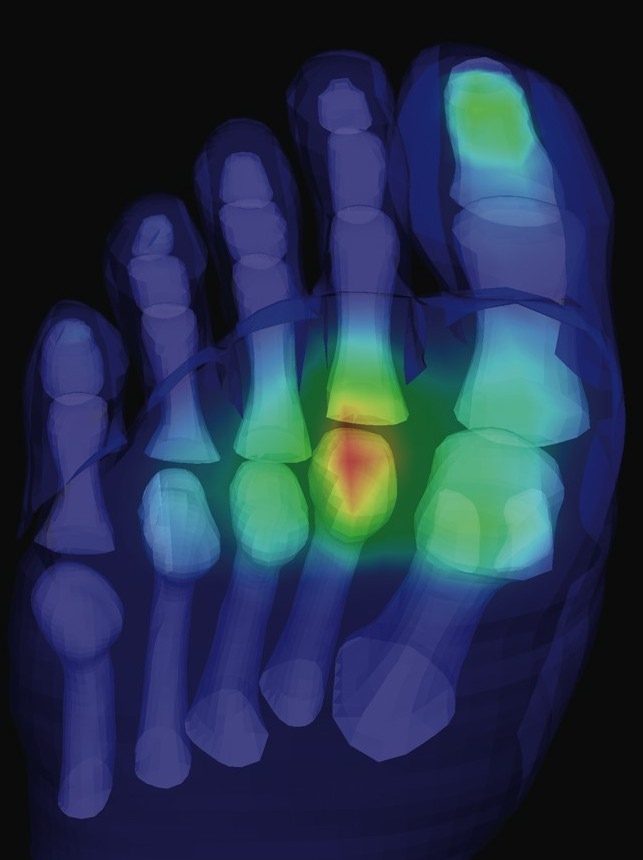

If you feel like you may be walking on a pebble in your shoe, or like there’s a rock underneath the ball of the foot, it may be a condition called capsulitis. Capsulitis is a common condition our podiatrists see and while it can affect any joint, it most commonly affects the second toe.

Like the name suggests, capsulitis means the inflammation (‘itis’) of a joint capsule. The joints in your feet are enveloped and contained within a capsule that helps the joint work smoothly and maintain a good alignment. When a capsule is damaged, the joint can become painful, swollen, and leave you feeling like you’re walking on a pebble. Capsulitis isn’t limited to the feet but can occur anywhere that a joint capsule is present, with a well-known capsulitis in the upper body being a frozen shoulder (adhesive capsulitis)

Joint pain arising from capsulitis is often caused by overloading the joint. This means that you place more pressure on the joint than it can handle, so damage occurs, and your pain starts. Your overloading is often linked to faulty foot mechanics, but may arise from wearing narrow, unsupportive or high-heeled shoes where the weight of your body is disproportionally loaded across the forefoot, going too hard too fast during physical activity, or abnormalities with your toe or foot structure or function. It’s not uncommon to find in a person with capsulitis of their second toe, that the second toe bone (metatarsal) is longer, and therefore takes on more pressure with each step, especially when pushing up off the ground.

Capsulitis is often accompanied by:

• Pain at the affected joint, especially when walking on it

• Swelling and warmth

• Redness around the joint

• Feeling like you’re walking on a pebble beneath the ball of your foot